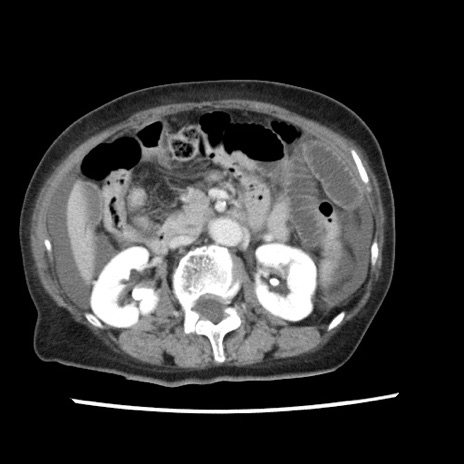

症例1(横断像)

【症例】80歳代女性

【主訴】腹痛

【現病歴】8時間前から腹痛あり来院。

【既往歴】糖尿病、脂質異常症、子宮体癌にて子宮全摘術

【身体所見】意識清明・会話良好だが腹痛で苦悶様、全腹部にわたって反跳痛と圧痛あり

【データ】WBC 13600、CRP 0.14、LDH 224、CK 90